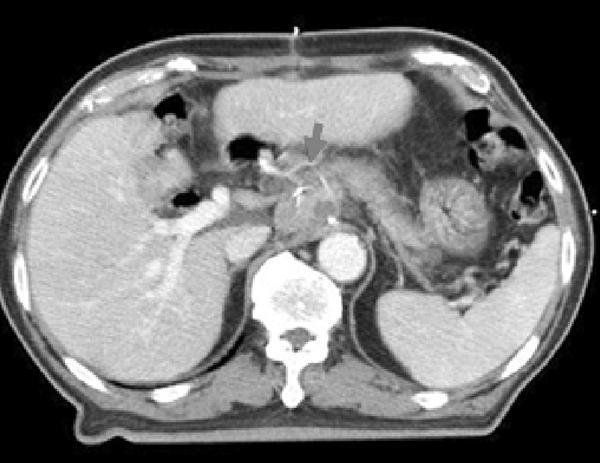

At 1 month after operation, the size of a retropancreatic node was increased and 18F-fluorodeoxyglucose (FDG) uptake was increased on PET-CT scan (Fig. 1). Therefore, radiotherapy was given to the draining abdominal lymph nodes and the metastatic node using 3D-CRT. Radiotherapy was given by three ports (anterior, posterior, and left) upto 45 Gy in 25 fractions from June to July 2006. On the dose-volume analysis, V30 of liver was less than 20% and V20 was 25%. Prior to irradiation, all the liver enzyme levels were within normal range (Child A) and chemotherapy was not added. During radiotherapy, CBC and liver function test were checked every week.

Fig. 1. 18F-fluorodeoxyglucose (FDG) PET/CT scan before abdominal irradiation. At 1 month after surgery, the size of the previously detected retropancreatic node was increased. The node also showed increased 18F-FDG uptake on 18F-FDG PET/CT scan (SUVmax=4.2). The arrows indicate the enlarged lymph node.